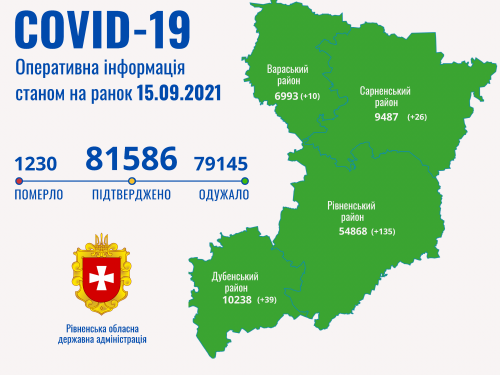

Коронавірус повертається: як стрімко зростає кількість хворих на Рівненщині (ВІДЕО)

Пів тисячі - у важкому стані, 9 жителів Рівненщини померли за добу від коронавірусу

Більше 3 тисяч випадків захворювання на коронавірус зафіксували в Україні за добу

COVID-19 на Рівненщині: 32 нових випадки, серед них 4 дітей, ще одна людина померла